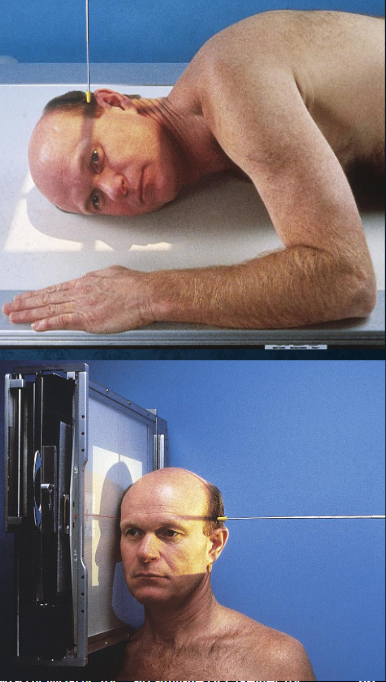

Lateral skull

patient position:

upright or semiprone

part position:

MSP of head parallel to IR

IPL perpendicular

IOML perpendicular to front edge of IR

respiration suspended

CR:

perpendicular to IR

enters 2 inches above EAM

collimation:

1 inch beyond skin line of the skull

Lateral skull image criteria

entire cranium without rotation or tilt

superimposed orbital roofs and greater wings of sphenoid

superimposed mastoid regions, EAMs, and TMJs

sella turcica in profile

penetration of parietal region

no overlap of c-spine by mandible